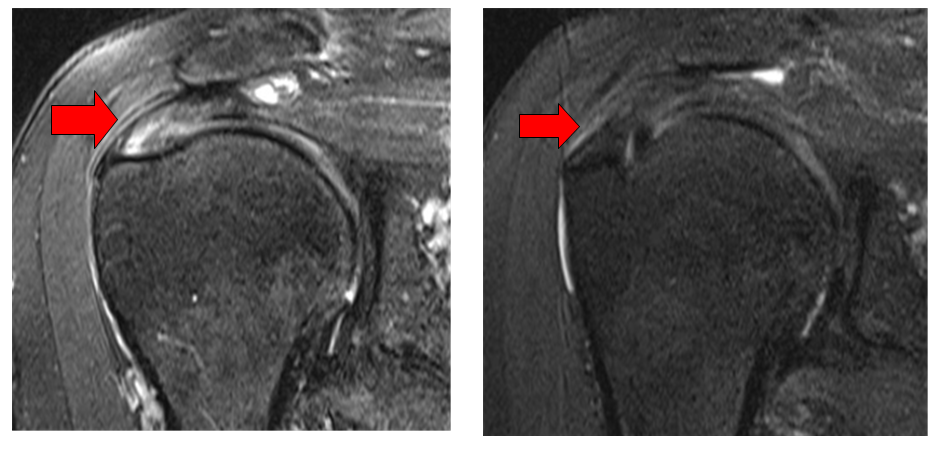

°¡Å縯´ëÇб³ ¼­¿ï¼º¸ðº´¿ø Á¤Çü¿Ü°ú ±è¾ç¼ö ±³¼ö(±³½ÅÀúÀÚ), ¿©Àǵµ¼º¸ðº´¿ø Á¤Çü¿Ü°ú ±èÁ¾È£ ±³¼ö(Á¦1ÀúÀÚ) ¿¬±¸ÆÀÀº ȸÀü±Ù°³ ºÎºÐ ÆÄ¿­ ȯÀڵ鿡°Ô ÆÄ¿­ ºÎÀ§¿¡ ÃÊÀ½ÆÄ À¯µµÇÏ ¾ÆÅÚ·ÎÄݶó°ÕÀ» ÁÖ»çÇÑ ÆÄ¿­ ºÎÀ§°¡ MRI °Ë»ç»ó ȸº¹µÆ°í ±â´ÉÀûÀ¸·Îµµ È£ÀüµÈ °ÍÀ» È®ÀÎÇß´Ù°í 23ÀÏ ¹àÇû´Ù.

¶Ç ÁÖ»ç 6°³¿ù ÈÄ ½ÃÇàÇÑ MRI °Ë»ç °á°ú 1mL Áֻ籺 Áß 36.7%, 0.5mL Áֻ籺 Áß 28.1% ¿¡¼­ ȸÀü±Ù°³ ÆÄ¿­ ºÎÀ§°¡ ȸº¹µÈ ¹Ý¸é Áֻ縦 ÇÏÁö ¾ÊÀº ±º¿¡¼­´Â ȸÀü±Ù °³ ÆÄ¿­ ȸº¹·üÀÌ 6.3%·Î Á¶»çµÆ´Ù.